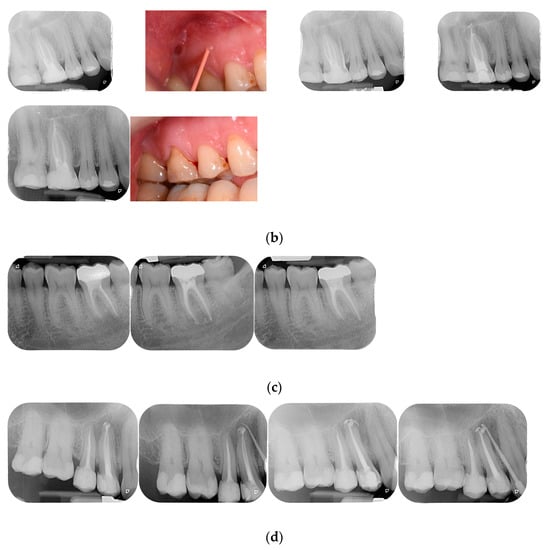

The clinical evaluation ‘success’ was referred to healed and healing categories and ‘failure’ to the not-healed teeth was classified as failure. Figure 1 show examples of each category. When a disagreement on the radiographic and/or clinical evaluation between the two evaluators was present, a discussion was made and a final consensus was reached. Examples of each outcome category are shown in Figure 1a–d.

Figure 1.

(a) Healed lower incisor at 12 months recall. (b) Healed upper first molar at 18 months recall. (c) A lower second molar in healing process after 6 months. (d) Not healed first upper bicuspid at 8 months recall.